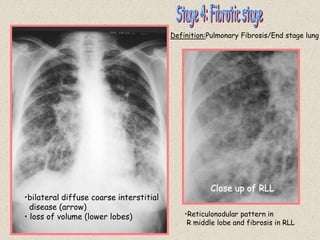

Definition:

•bilateral diffuse coarse interstitial

disease (arrow)

• loss of volume (lower lobes) •Reticulonodular pattern in

R middle lobe and fibrosis in RLL

Definition:Pulmonary Fibrosis/End stage lung